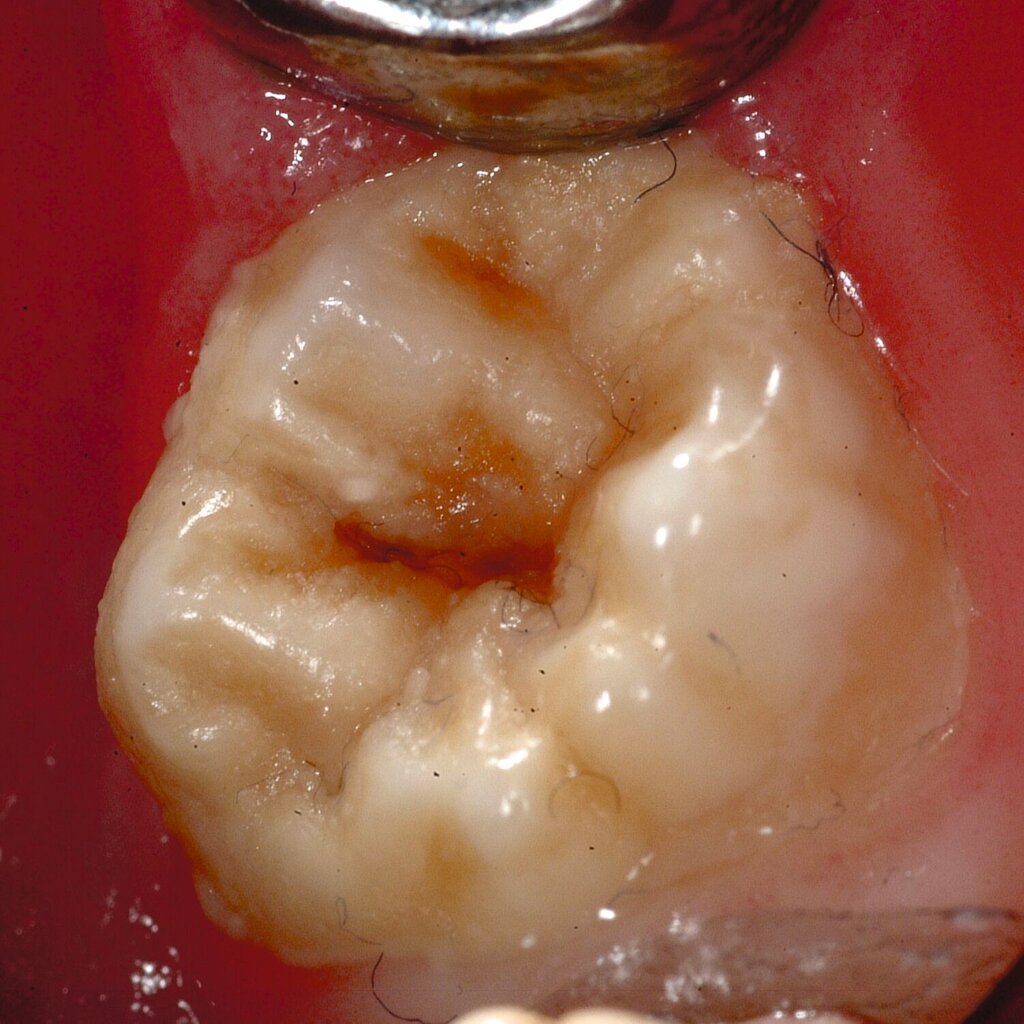

Das klinische Erscheinungsbild an bleibenden Zähnen zeigt typischerweise weißlich-gelbe bis gelblich-braune Opazitäten, die zumindest in einigen Bereichen durch eine scharfe Abgrenzung (engl.:„demarcated opacities“) zum gesunden Zahnschmelz charakterisiert sind (Abbildungen 3 und 4). Die abgegrenzten Hypomineralisationen befinden sich mehrheitlich im Bereich der inzisalen Kronenhälfte unabhängig von dem Auftreten an Front- oder Seitenzähnen. Die Ausprägung am Zahn kann dabei auf einzelne Areale oder Höcker begrenzt sein.

Für die Dokumentation und Klassifikation der MIH wurden verschiedene Systeme vorgeschlagen. Als historisch und veraltet gilt der (modifizierte) DDE-Index. Demgegenüber haben die Kriterien der EAPD – abgegrenzte Opazitäten (Abbildung 3 und 4), Schmelzeinbrüche (Abbildung 5), atypische Restaurationen (Abbildung 6) – mittlerweile die weiteste Verbreitung gefunden. Diese wurden 2003 erstmals zur Beschreibung der MIH auf empirischer Basis publiziert [Weerheijm et al., 2003] und den Jahren 2010 und 2022 im Rahmen der damaligen MIH-Workshops bestätigt [Lygidakis et al., 2010; 2022].